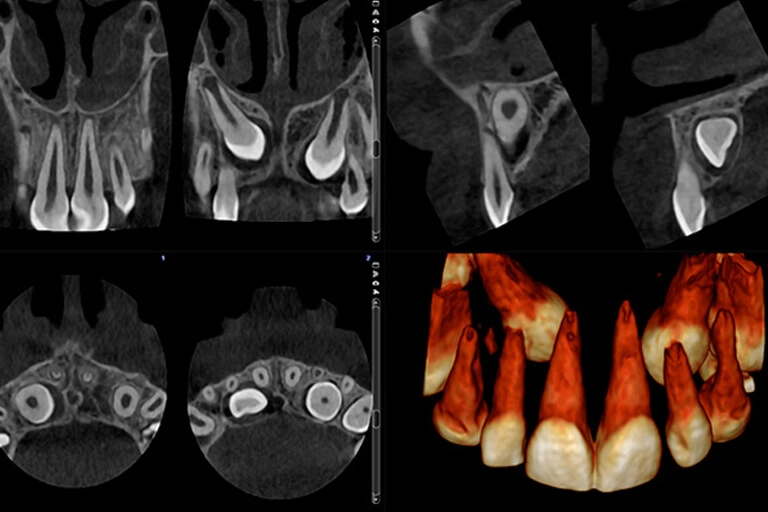

3D Scan of your teeth, jaws, airway, and joints in one complete and highly detailed image!

Our Dental office only uses the most advanced and newest dental equipment available on the market. A dental cone beam CT scanner (CBCT scanner) is a special type of dental x-ray machine capable of producing a three-dimensional (3D) scan of your teeth, jaws and joints in one image. This helps diagnose potential issues more accurately and provide treatment with unprecedented confidence. This is especially useful for dental implant surgery, where it allows for precise treatment planning and faster surgery with less pain.

We use it for 100% of our implant patients for maximum safety and predictability. It is also highly useful for patients with pain that sometimes is not evident on traditional 2D X-rays. We have done many 2nd opinions where the referring dentist could not find the source of the pain. With a 3D X-ray we were immediately able to see where the infection was, and could start treatment right away. It is also helpful for root canal procedures, allowing us to visualize the location of your nerve inside the tooth. It can also perform an airway analysis to help with sleep apnea treatment.